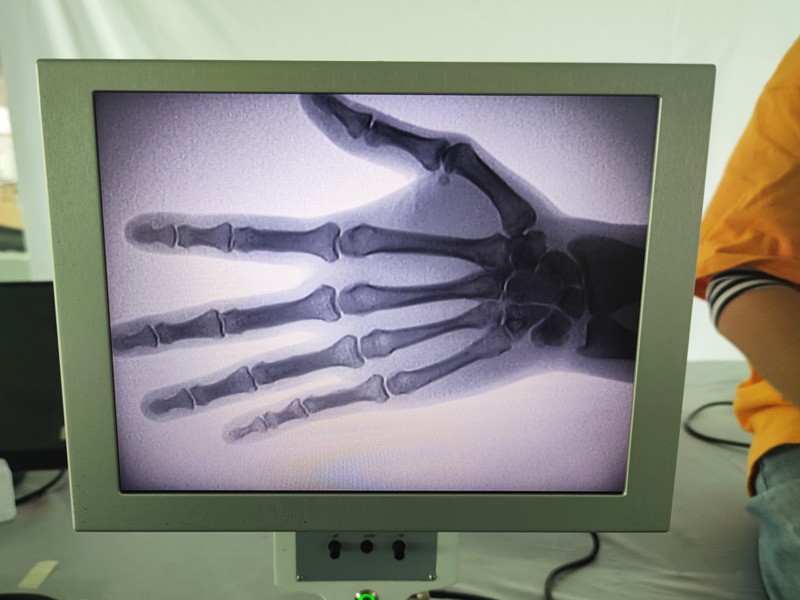

As-c200 bärbar röntgenmaskin är ett bärbart instrument med liten stråldos och mycket säker. Den är särskilt lämplig för enheter och individer med otillräcklig budget och låga krav på bilder. Den nya generationen är utrustad med en 10 tums högupplöst stor skärm, som har ett större perspektivområde och kan perspektivera hela handflatan fullt ut. Det är mest lämpligt för medicinskt ortopediskt perspektiv. Den kan kopplas till en filmskrivare för att skriva ut ortopediska filmer, och kan även användas i industriell produktion och testning. Inget mörkrum, direkt perspektiv, omedelbar observation, hög upplösning och tydlig bild.

3. Stor bildskärm: Maskinen har en stor bildskärm som ger ett effektivt arbetsflöde och enkel identifiering av kritiska fynd.

Vår ortopedisk röntgenmaskin är en högkvalitativ produkt som designades speciellt för ortopedisk bildbehandling. Den kan användas för diagnos och behandlingsplanering av olika ortopediska tillstånd, inklusive frakturer, dislokationer, artrit och bentumörer. Den är utrustad med avancerad röntgenteknik som möjliggör högkvalitativa bilder med reducerad strålningsexponering. Maskinen har ett högupplöst bildsystem och kan ta bilder av vilken benstruktur som helst med stor tydlighet.